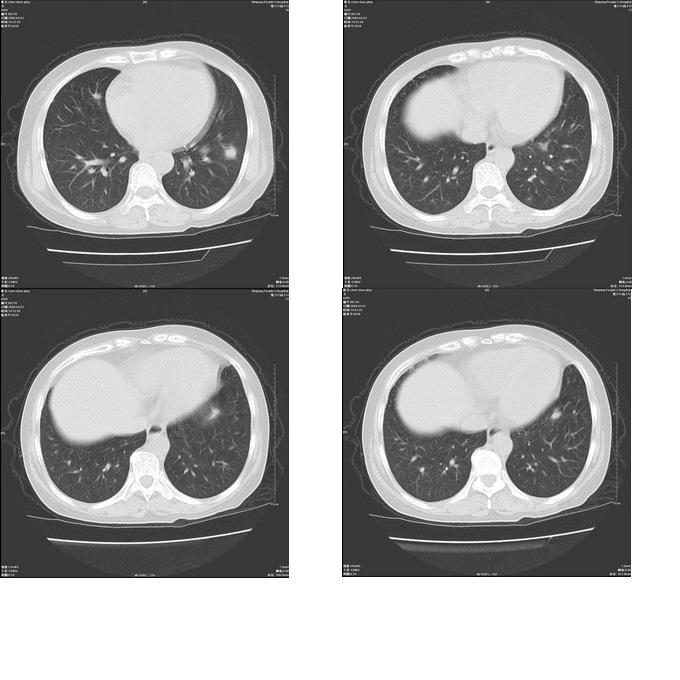

患者,女,48岁,发热伴陈发性咳嗽5天,偶尔痰中带血。体温约38°~40°;白细胞明显减低0.85x10的9次方/升。入院后抗炎、抗痨一周复查病灶明显进展。

右上肺后段实变影,内见支气管气象,肺门未见软组织肿块,气管前方有肿大淋巴结。左下肺见多个类圆形结节影。考虑:1.右上肺后段大叶性肺炎,需进一步检查病原体种类,应多询问病史,条件许可考虑做纤支镜检查2.左下肺结节影性质待定

考虑右上肺后段大叶性肺炎不除外结核,伴双肺结节播散灶,希定期复查。